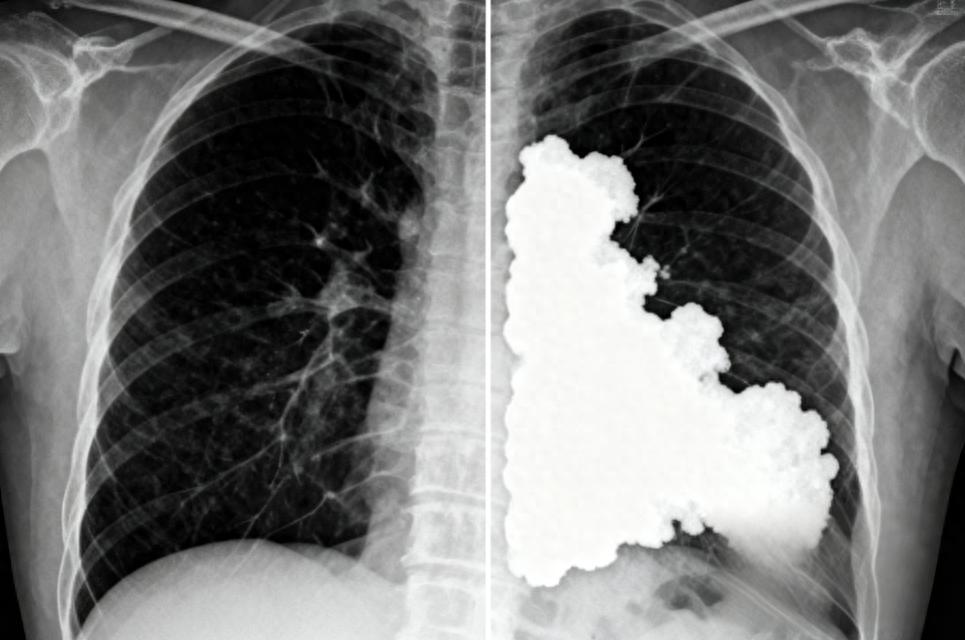

先澄清:“白肺” 不是病名,是醫生看 X 光片時的 “黑轉白” 現象 ——

- 正常的肺裏全是空氣,X 光片上是黑乎乎的;

- 一旦流感病毒攻進肺部,引發嚴重炎症,肺泡就會被炎性液體、黏痰甚至膠凍狀的痰栓填滿,像泳池被泥沙堵死、水管被冰雕塞住,X 光片上就會出現大片白色區域。

這白色面積越大就越危險:超過 70% 的肺變白,意味着大部分肺泡沒法呼吸,人就會像溺水一樣缺氧,幾小時內可能呼吸衰竭!